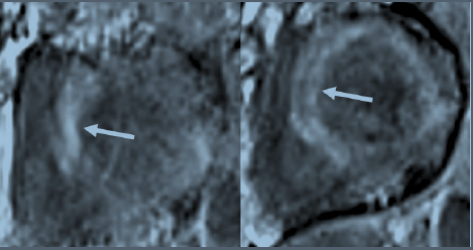

Myocarditis is an inflammatory disorder of the myocardium that in the past often required a histologic diagnosis after myocardial biopsy. In recent decades, diagnostic criteria have shifted to noninvasive testing, including highly sensitive troponin measurement and cardiac MRI, reserving biopsy for more diagnostically ambiguous cases. MRI criteria for diagnosing myocarditis include intense signal after gadolinium enhancement, which results from hyperemia; increased myocardial T2 relaxation time or intensity associated with myocardial edema; and late gadolinium enhancement, indicating necrosis or fibrosis (Figure 3).

Late gadolinium-enhanced images of short-axis views of the left ventricle. Arrows show diffuse patchy areas of enhancement consistent with myocardial necrosis and/or fibrosis. Images were obtained from a patient with acute myocarditis associated with COVID-19 pneumonia.

Short-axis MRI scan of left ventricle after gadolinium enhancement. T2 mapping of this slice shows heterogeneous myocardial edema (arrow). This image was obtained from a patient with acute myocarditis complicating COVID-19 pneumonitis.